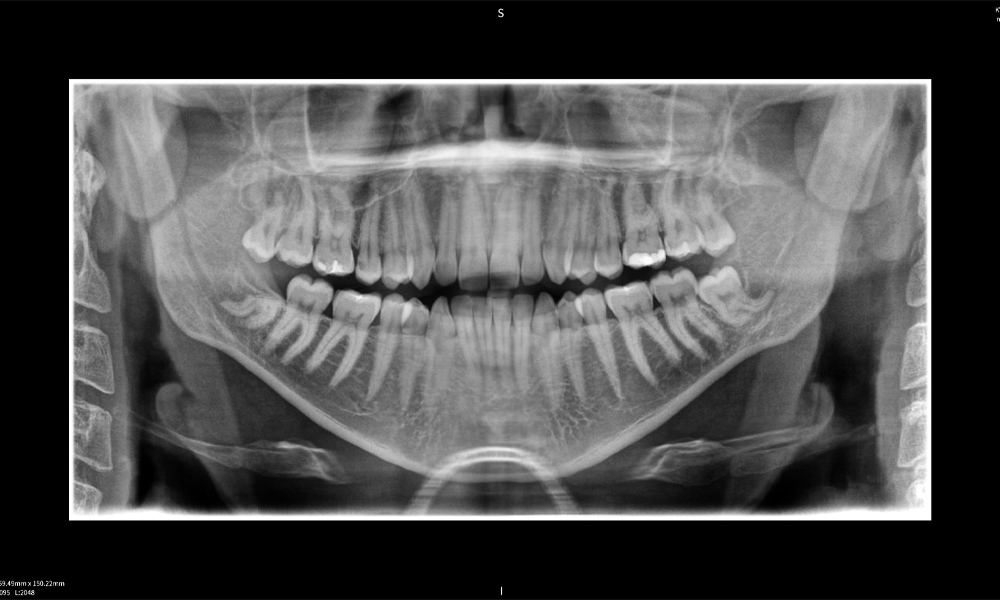

Below you will find a case from Dr. med. dent. Oliver A. Centrella, in which the CBCT images obtained with Seethrough Max provided crucial information on the complex anatomy and the critical relationship between the wisdom teeth and the inferior alveolar nerve. In this case, there is a indication for the surgical removal of the wisdom teeth.

Figure e: The panoramic X-ray serves as an initial assessment tool, showing the general positioning of the teeth as well as any potential pathological changes. Notably, on the right side (tooth 48), the situation following a crown amputation performed by an external practitioner is visible. The two severely curved roots remain in close topographical proximity to the inferior alveolar nerve within the bone. This suggests a deliberate decision to avoid the increased risk of nerve injury during a complete extraction, and represents a clinically relevant finding. In summary, CBCT scans with Seethrough Max, provide crucial information about the complex anatomy and the critical relationship between the wisdom teeth and the inferior alveolar nerve. This detailed preoperative diagnostic imaging is essential for safe and successful surgical procedures in the mandibular region.